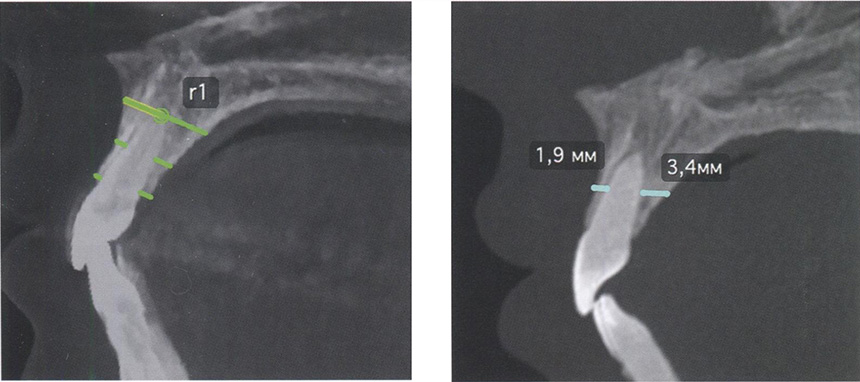

С целью оценки положения зубов на компьютерных томограммах по-явилась возможность проводить линейные измерения внутри альвеолярного(-ой) отростка/части челюстей, тем самым определять границы возможных перемещений (рис. 81).

Оценка положения резцов на компьютерных томограммах с помощью линейных параметров

Рис. 81. Оценка положения резцов на компьютерных томограммах с помощью линейных параметров между альвеолярным отростком верхней челюсти и корнем зуба 2.1 в области апексов, на уровне середины корня и гребне альвеолярного отростка

На компьютерных томограммах стало возможным проводить анализ положения корней зубов боковой группы, каждого в отдельности, с помощью как линейных, так и угловых параметров (рис. 83). Среди угловых измерений отдельных зубов можно сопоставить ось отдельного зуба с осью альвеолярного(-ой) отростка/части исследуемого зубочелюстного сегмента (рис. 84).

Оценка положения зуба

Рис. 83. Оценка положения зуба 1.6 на компьютерных томограммах с помощью: а — углового параметра /_u6/JJ; б — линейных параметров между альвеолярным отростком верхней челюсти и корнем зуба в области апексов, на уровне фуркации и гребне альвеолярного отростка

Методология проведения измерений по компьютерным томограммам

Рис. 84. Оценка положения зуба 1.5 на компьютерных томограммах с помощью линейных и углового параметров внутри альвеолярного отростка верхней челюсти